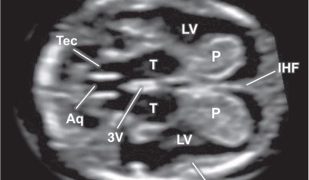

Anche a Dicembre un nuovo Journal Club relativo ad un nuovo segno ecografico in caso di Placenta Accreta Spectrum. Grazie a Gabriele Saccone! Buona Lettura! [pdf-embedder url="https://www.sieog.it/wp-content/uploads/2021/12/Journal-club-dicembre-2021.pdf" title="Journal club -...